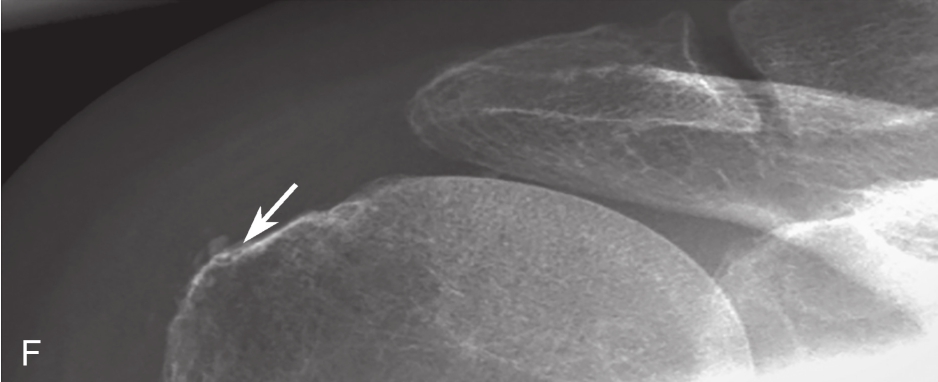

A.右侧冈上肌腱内钙化灶;B.超声引导下穿刺冲洗;C.注射器内为抽出的钙化灶,呈乳白色黏稠液体;D.生理盐水反复多次冲洗,可见冲洗液体逐渐变清亮;E.介入治疗前钙化灶X线片;F.治疗后钙化灶明显缩小;箭头:钙化灶